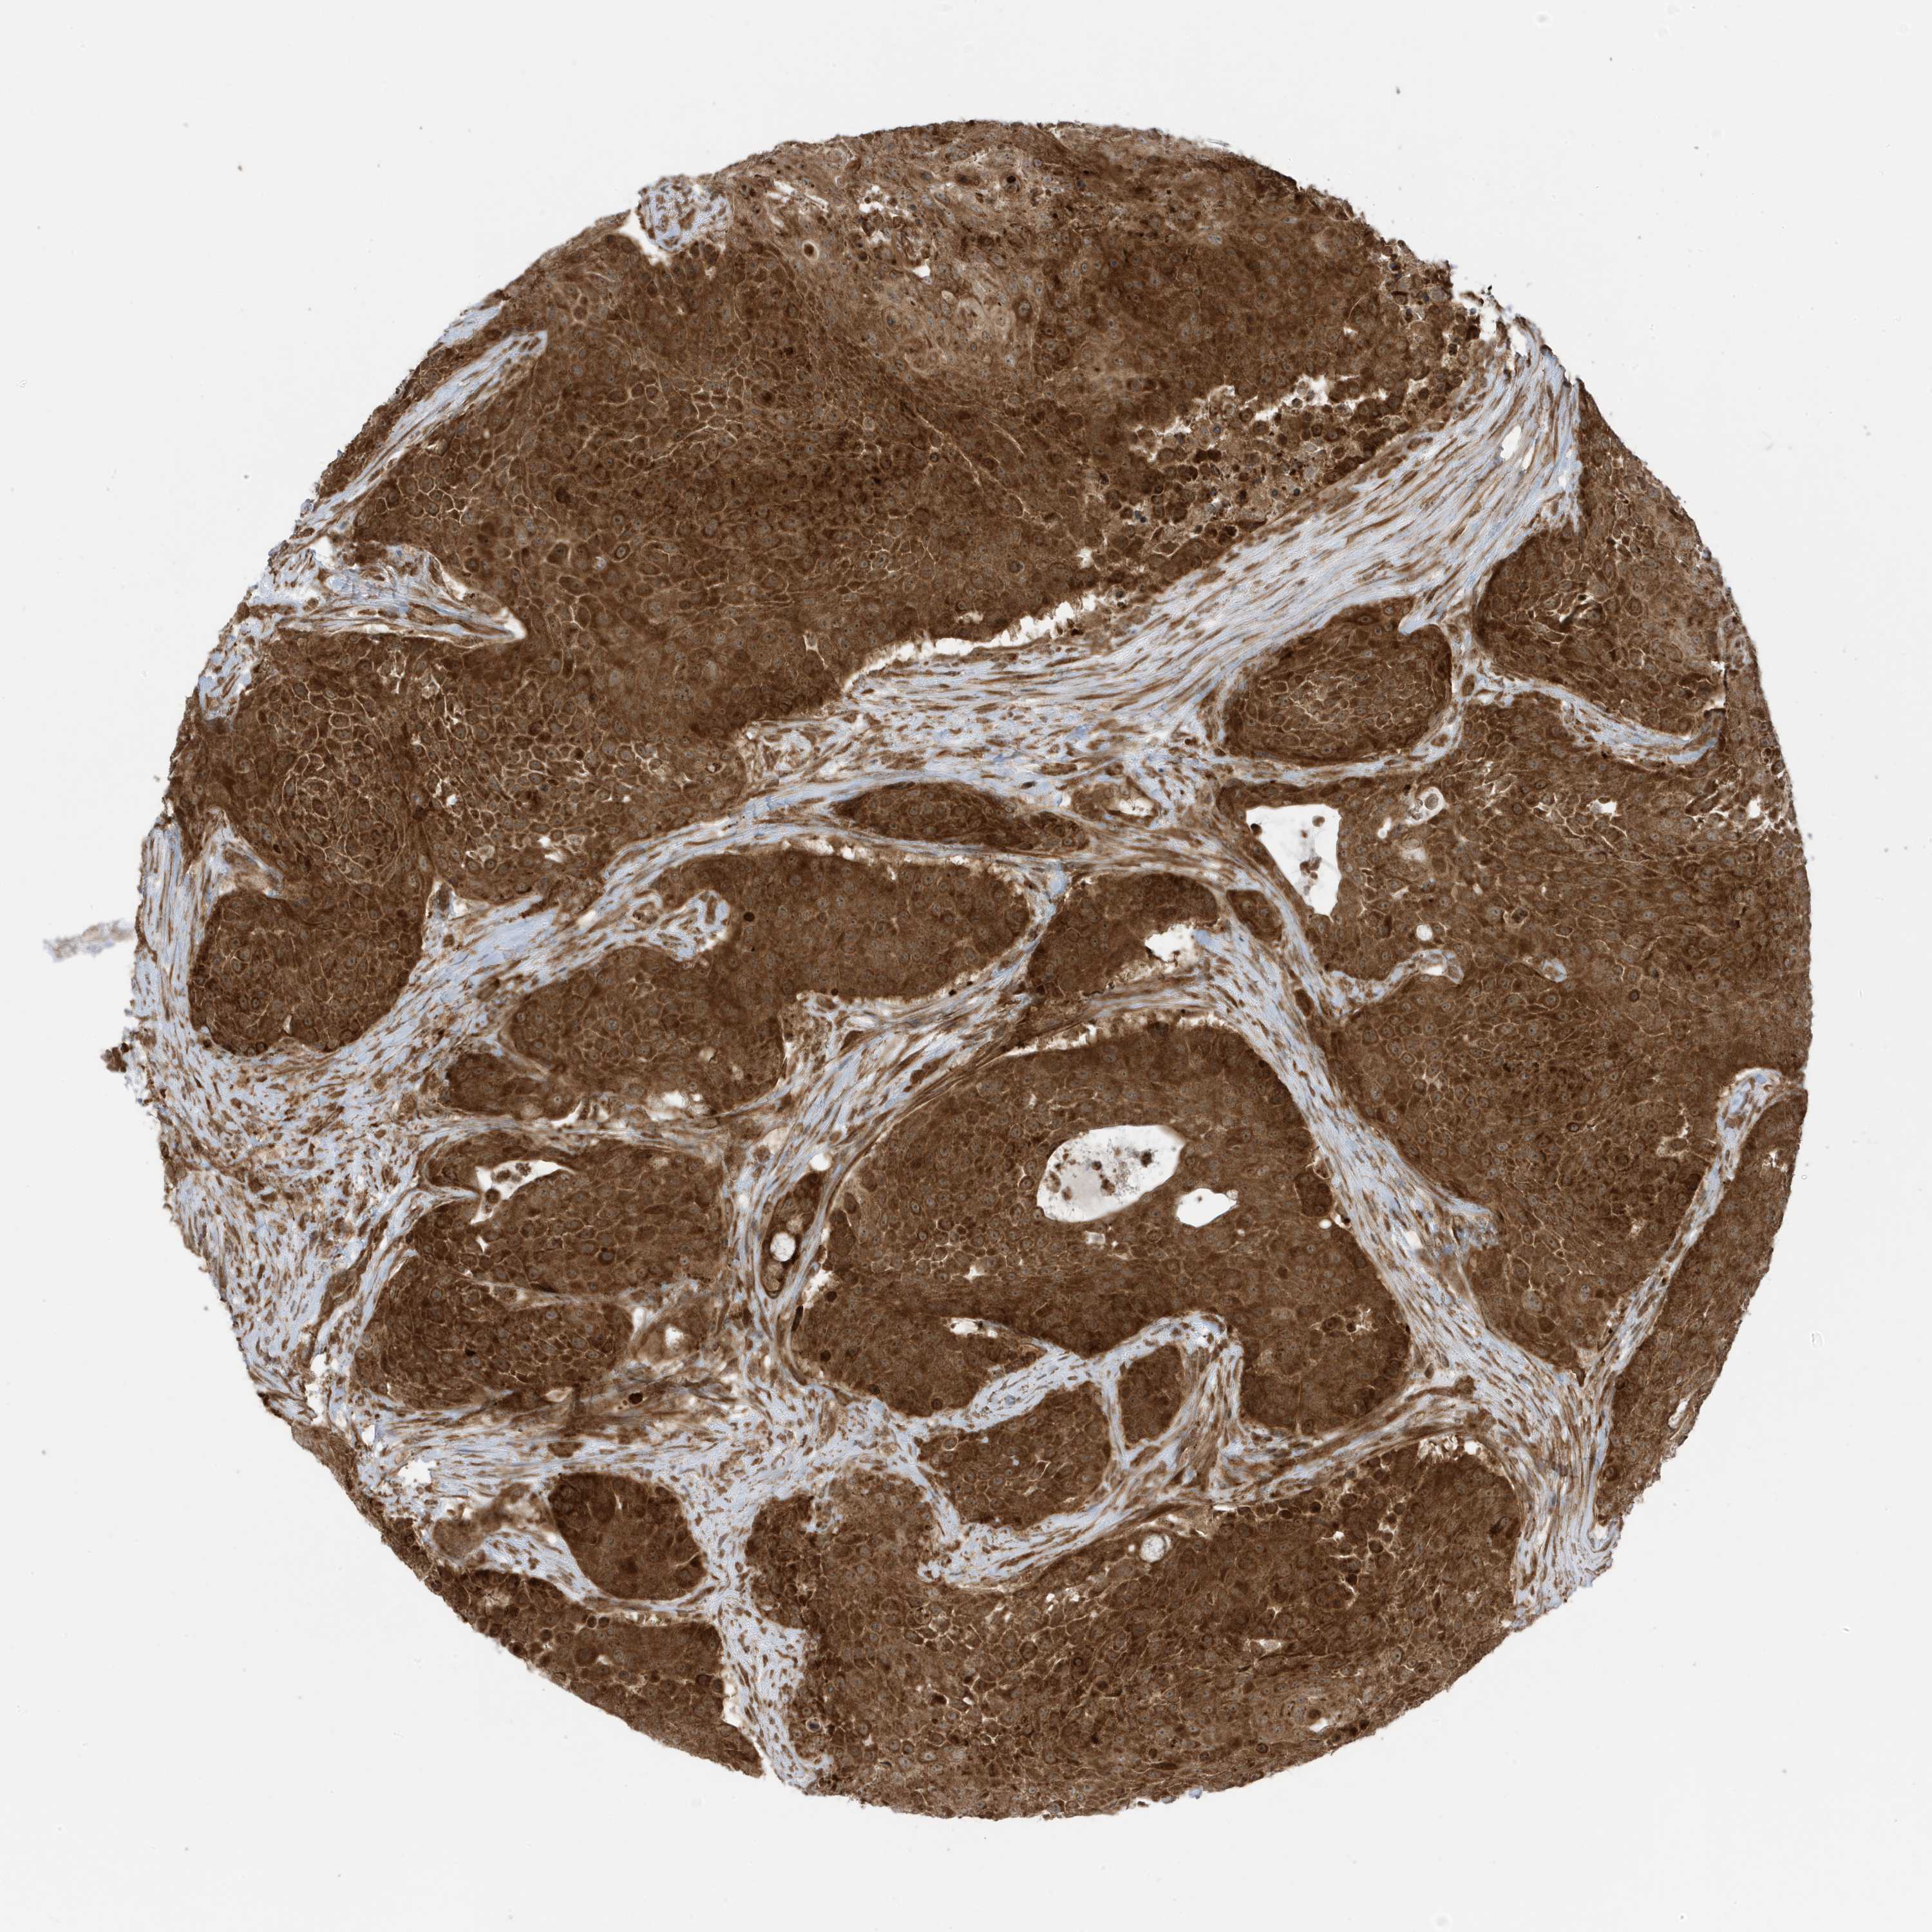

UROTHELIAL CANCER - Protein expressioni

A mouse-over function shows sample information and annotation data. Click on an image to view it in a full screen mode. Samples can be filtered based on level of antibody staining by selecting one or several of the following categories: high, medium, low and not detected. The assay and annotation is described here.

Antibody stainingi

Antibody staining in the annotated cell types in the current human tissue is reported as not detected, low, medium, or high, based on conventional immunohistochemistry profiling in selected tissues. This score is based on the combination of the staining intensity and fraction of stained cells.

Each image is clickable and will lead to virtual microscopy that enables deeper exploration of all samples and also displays staining intensity scores, fraction scores and subcellular localization as well as patient and tissue information for each sample.

Antibody HPA035399

Staining

High

Medium

Low

Not detected

Intensity

Strong

Moderate

Weak

Negative

Quantity

>75%

75%-25%

<25%

None

Location

Nuclear

Cytoplasmic/membranous

Cytoplasmic/membranous,nuclear

Urothelial carcinoma, Low grade

Urothelial carcinoma, High grade